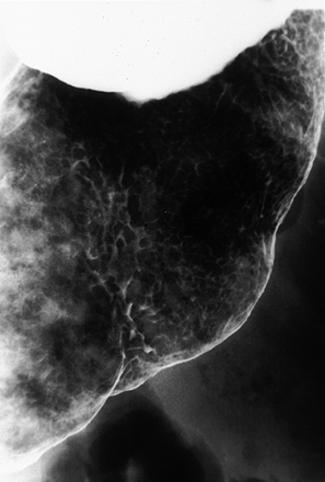

A case of so-called early gastric malignant lymphoma which characteristically showed various features.

[ Image ID:9127 ]

Malignant Lymphoma/Malignant lymphoma

Stomach/More than one of above

X-ray

40 -

submucosa